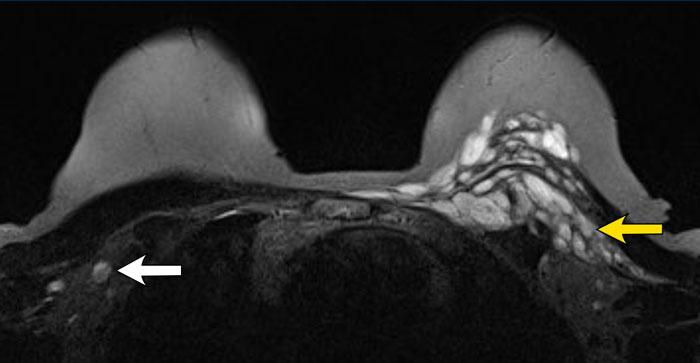

BIA-ALCL

BIA-ALCL (u lympho tế bào lớn dạng nguyên bào liên quan đến túi ngực) là một biến chứng quan trọng cần lưu ý đối với các túi ngực độn silicon và nước muối sinh lý.

BIA-ALCL phát triển chủ yếu, nếu không muốn nói là hoàn toàn, ở những bệnh nhân có túi ngực bề mặt nhám.

Tỷ lệ lưu hành ước tính ở nhóm túi ngực này là 1:30.000.

Phần lớn các trường hợp BIA-ALCL được ghi nhận trên túi ngực bề mặt nhám Allergan Biocell và loại túi này sau đó đã bị thu hồi khỏi thị trường.

Hai phần ba bệnh nhân BIA-ALCL biểu hiện bằng triệu chứng khó chịu và sưng nề do sự hình thành tràn dịch quanh túi ngực (85%), trong đó phát hiện các tế bào lympho không điển hình. Đôi khi có kèm theo khối u trong 15% trường hợp.

Bất kỳ trường hợp tràn dịch hoặc khối u một bên xuất hiện muộn nào cũng cần được chọc hút và phân tích tế bào học.

Phân giai đoạn bệnh được thực hiện bằng PET-CT, tương tự như các loại u lympho khác.

Phần lớn bệnh nhân được chẩn đoán ở Giai đoạn 1.

Phương pháp điều trị là phẫu thuật cắt bỏ túi ngực, bao xơ và khối u (nếu có).

Tiên lượng thuận lợi khi được điều trị sớm.